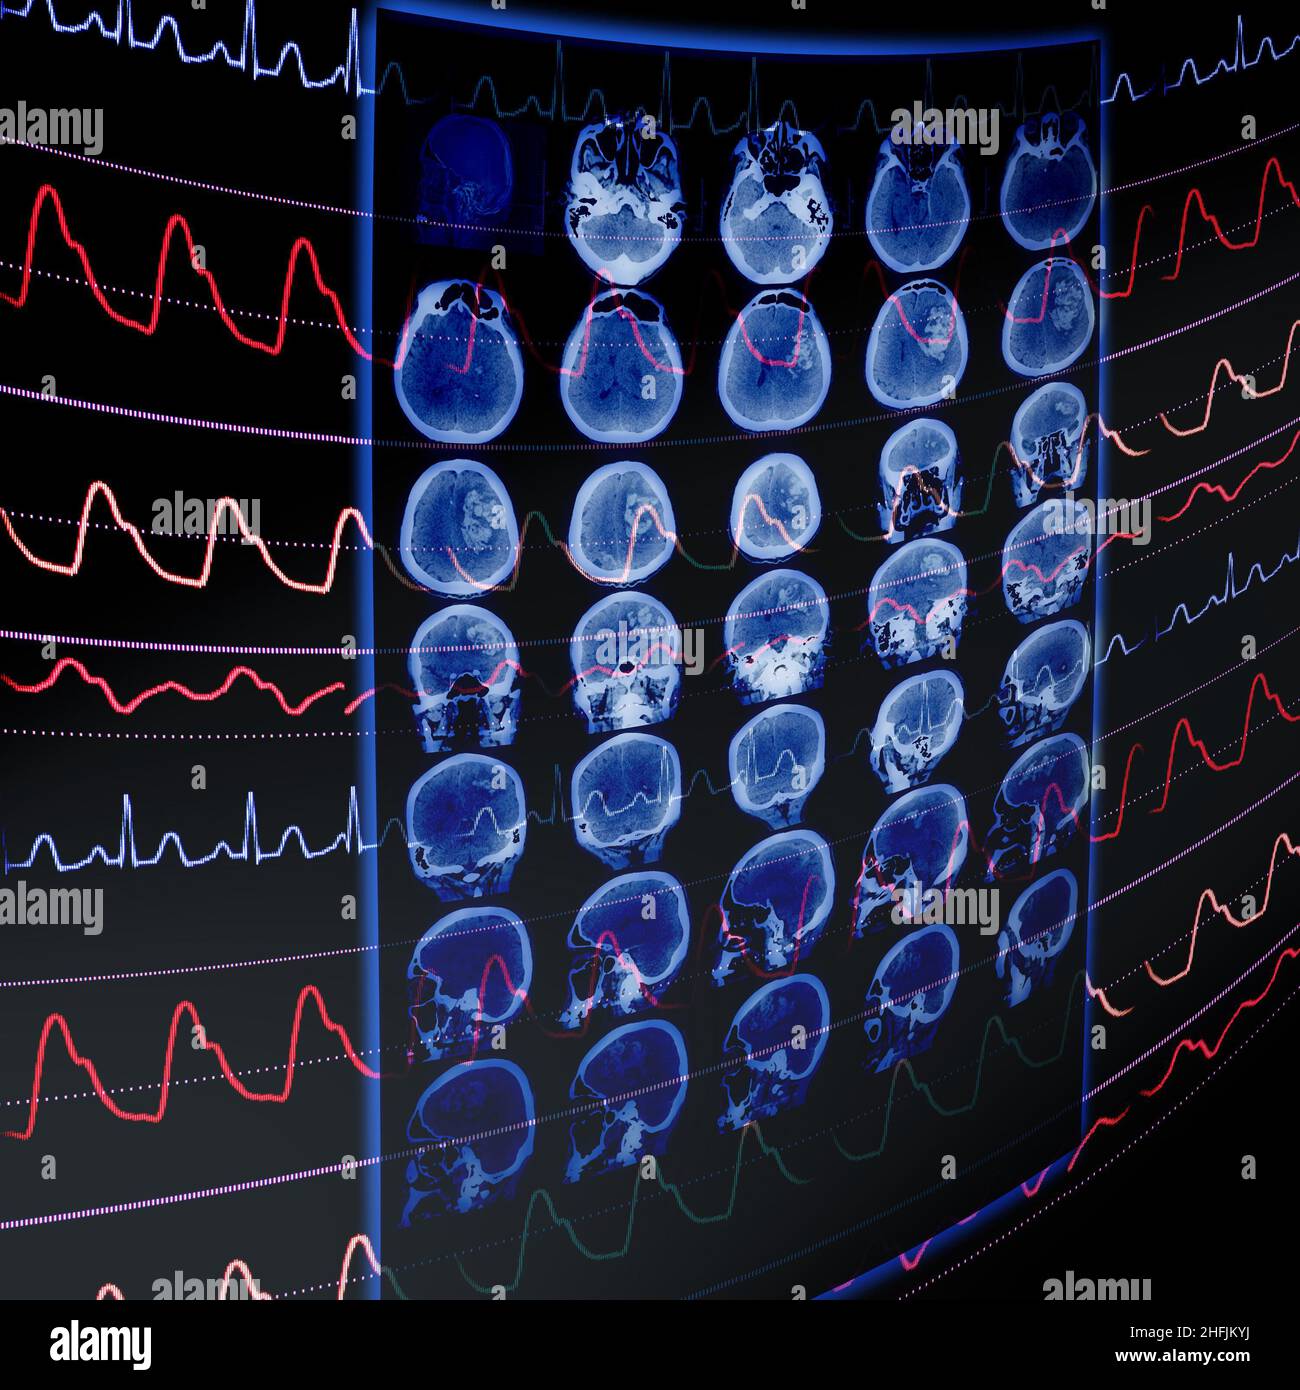

CT film and ECG monitoring as a medical concept of early vascular disease detection. Stock Photohttps://www.alamy.com/image-license-details/?v=1https://www.alamy.com/ct-film-and-ecg-monitoring-as-a-medical-concept-of-early-vascular-disease-detection-image457100008.html

CT film and ECG monitoring as a medical concept of early vascular disease detection. Stock Photohttps://www.alamy.com/image-license-details/?v=1https://www.alamy.com/ct-film-and-ecg-monitoring-as-a-medical-concept-of-early-vascular-disease-detection-image457100008.htmlRF2HFJKM8–CT film and ECG monitoring as a medical concept of early vascular disease detection.

CT film and ECG monitoring as a medical concept of early vascular disease detection. Stock Photohttps://www.alamy.com/image-license-details/?v=1https://www.alamy.com/ct-film-and-ecg-monitoring-as-a-medical-concept-of-early-vascular-disease-detection-image457100214.html

CT film and ECG monitoring as a medical concept of early vascular disease detection. Stock Photohttps://www.alamy.com/image-license-details/?v=1https://www.alamy.com/ct-film-and-ecg-monitoring-as-a-medical-concept-of-early-vascular-disease-detection-image457100214.htmlRF2HFJKYJ–CT film and ECG monitoring as a medical concept of early vascular disease detection.